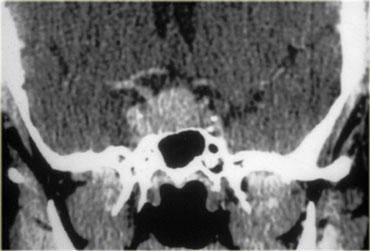

Đây là các hình ảnh CT của một hamartoma treo từ sàn não thất ba.

Tổn thương không ngấm thuốc sau khi tiêm thuốc cản quang tĩnh mạch.